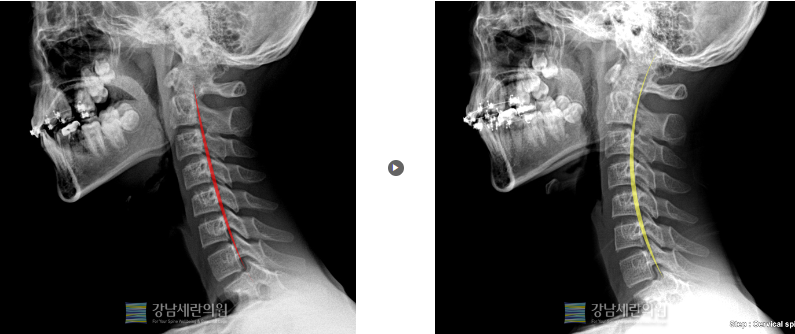

#일자목

일자목 교정 전 ▶ 일자목 30회(3개월) 치료 후